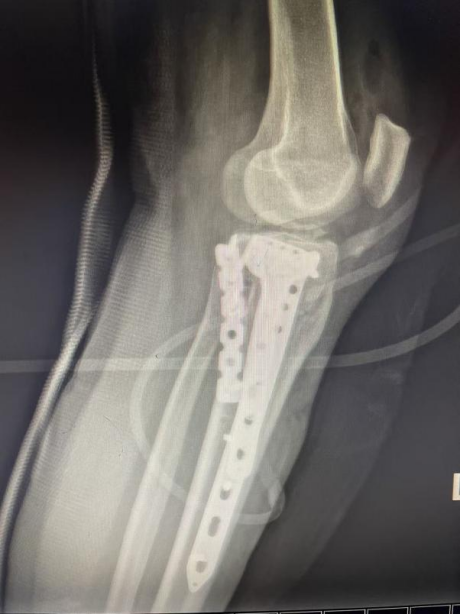

传统治疗手段对于此类骨折往往束手无策,极易导致关节僵硬、畸形愈合、慢性疼痛和继发性关节炎。面对如此复杂的损伤,我院骨科在

南医三院创伤骨科副主任医师杨诚的协助下迅速为张女士成功实施了

胫骨平台骨折切开复位钢板螺钉内固定术。

术后影像显示:患者胫骨平台的关节面高度、宽度及下肢力线得到很好恢复,内固定位置精准牢固。目前,张女士在康复师指导下已开始进行早期的、安全的关节活动度训练,为未来的功能恢复奠定了坚实基础。

(术后图)